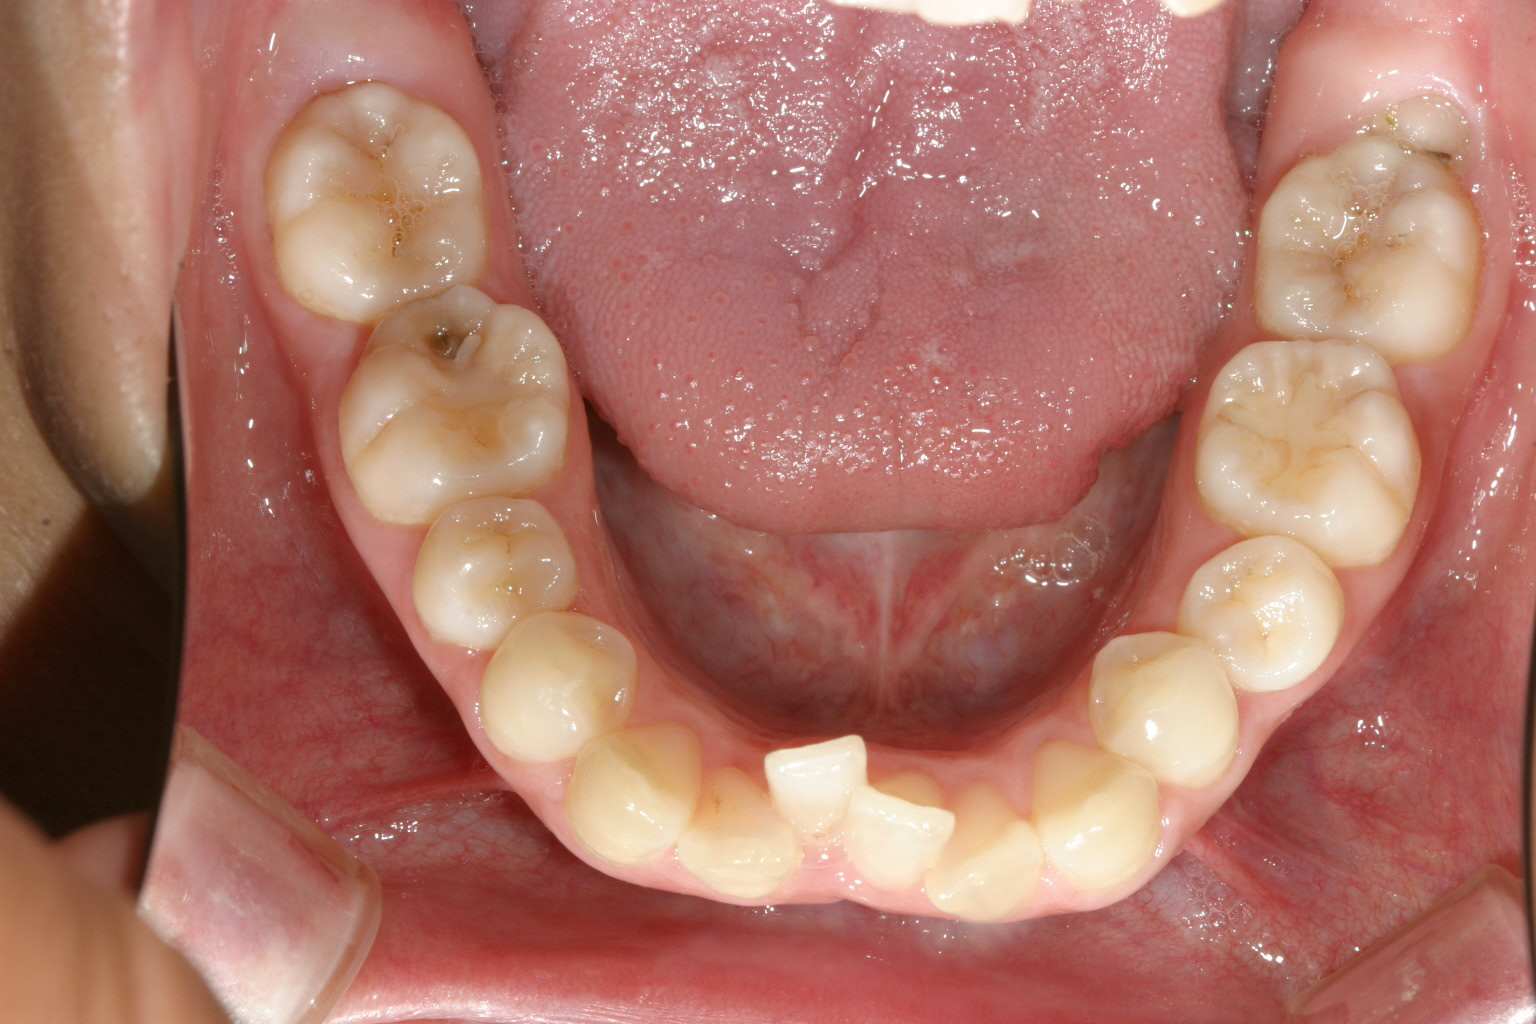

前歯が翼状捻転しています。

下顎前歯に叢生が見られます。